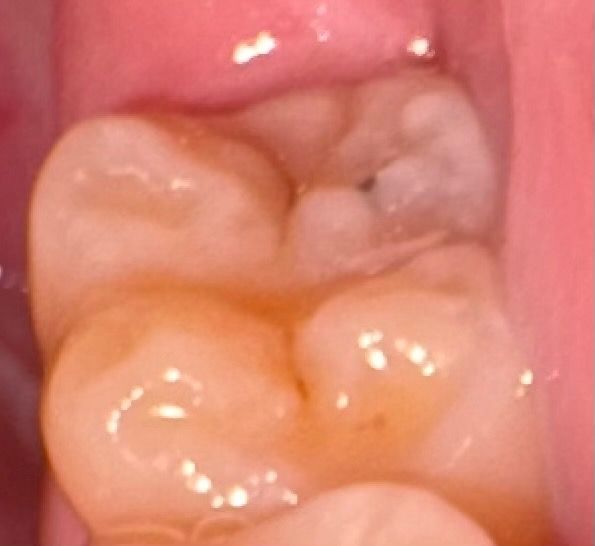

충치같은데 이정도면 신경치료 받아야하나요

통증 있었던 적은 없고 예전엔 어금니 위에 까만 점만 있었는데 이제는 옆면이 어둡게 되었더라고요 내부까지 충치 퍼진것같은데 신경치료 해야하나요

• 1번 째 사진

충치는 명확히 있는 것으로 판단되며 빠른 시일내에 치료를 받는 것이 필요해보이는 상황입니다.

정확한건 치과에 가셔서 엑스레이를 찍어봐야 알겟지만 신경치료 까지는 안하셔도 될것같습니다

통증 있었던 적은 없고 예전엔 어금니 위에 까만 점만 있었는데 이제는 옆면이 어둡게 되었더라고요 내부까지 충치 퍼진것같은데 신경치료 해야하나요 -> 생각보다 파보면 깊을 것 같습니다 신경치료 가능성도 있습니다